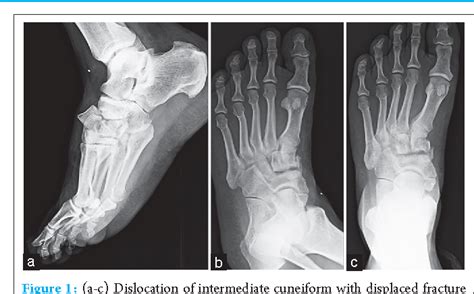

Plantar Dislocation Of The Middle Cuneiform Bone With Medial Cuneiform Subluxation: A Case Report

(pdf) isolated plantar dislocation of intermediate cuneiform : a case.